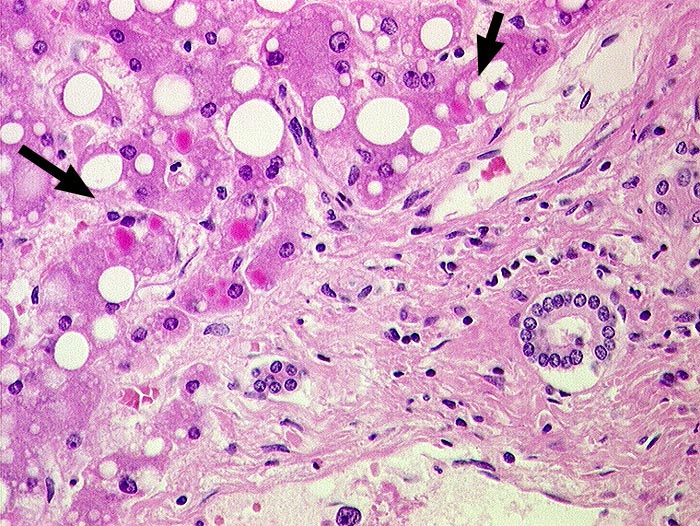

► Eosinophile Zytoplasmaeinschlüsse in periportalen Hepatozyten. Grobtropfige Verfettung.

alpha-1 Antitrypsin Typ Piz